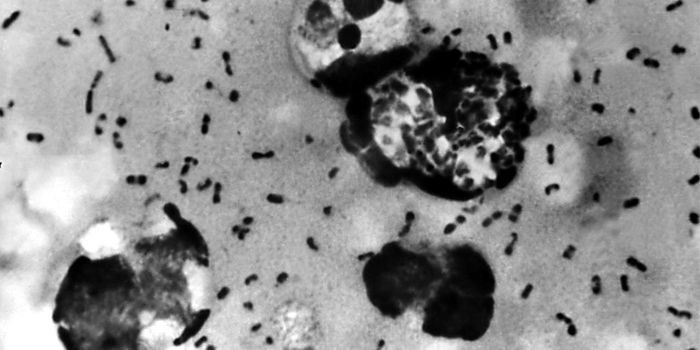

Follow a curation of discoveries and updates in immunology focusing on immune responses to infectious disease, structure and function, and developments in the defense against infection.